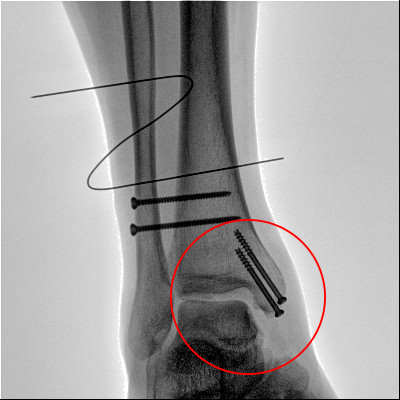

踝關節骨折在X影像上的表現有很多種。如內踝骨折和外踝骨折,我們可以在影像上看到骨折處的骨折線是不連續的。還有后踝的骨折,內踝、外踝、后踝聯合在一起發生的骨折,我們稱之為“三踝骨折”,這些都是在X影像上能夠顯示出來的。

內踝骨折

外踝骨折

后踝骨折

三踝骨折